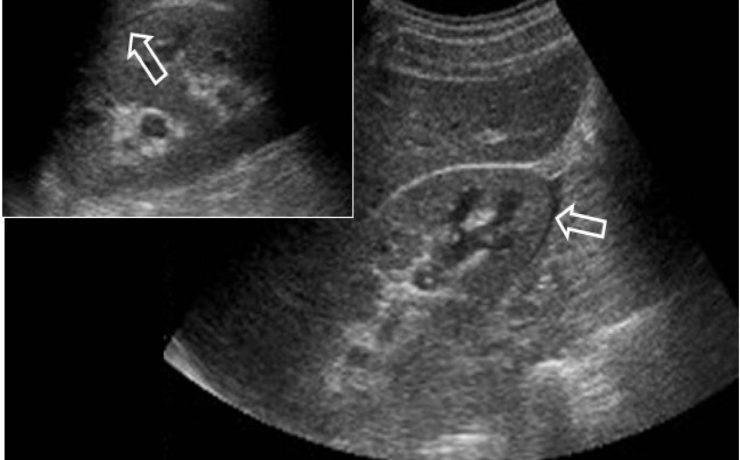

Síndrome de rokitansky y fibroma pélvico

El síndrome de Rokitansky, es la anomalía más grave del tracto reproductivo femenino. Consiste en la ausencia congénita de vagina y útero ausente o rudimentario, como consecuencia de la falla en el desarrollo Mûlleriano de la vagina y el útero. Este síndrome fue descrito por Rokitansky en 1838. Es la